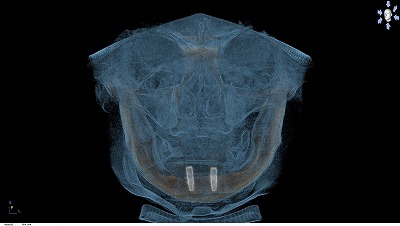

動かない総義歯(インプラントオーバーデンチャー)

あごの土手が減ってしまった患者さんで、動かない入れ歯がほしい!もっと強く咬みたい!方には「インプラントオーバーデンチャー」。 下あごに2本のインプラントを植えて、クリップや磁石で義歯をとめます。

ベルギーやオランダでは保険に導入されているほど信頼のある治療法で、 世界的に認められているエビデンス(科学的根拠)があります。